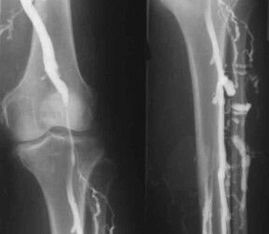

The most common instrumental diagnostic method is the use of ultrasound examination of the venous vessels of the legs.This technique allows you to visualize the vascular system and identify the degree of progress of the pathological process.

- Phlebography.

- Photoplethysmography.

The use of venous occlusion plethysmography allows you to determine the volume of blood in the veins of the lower extremities.